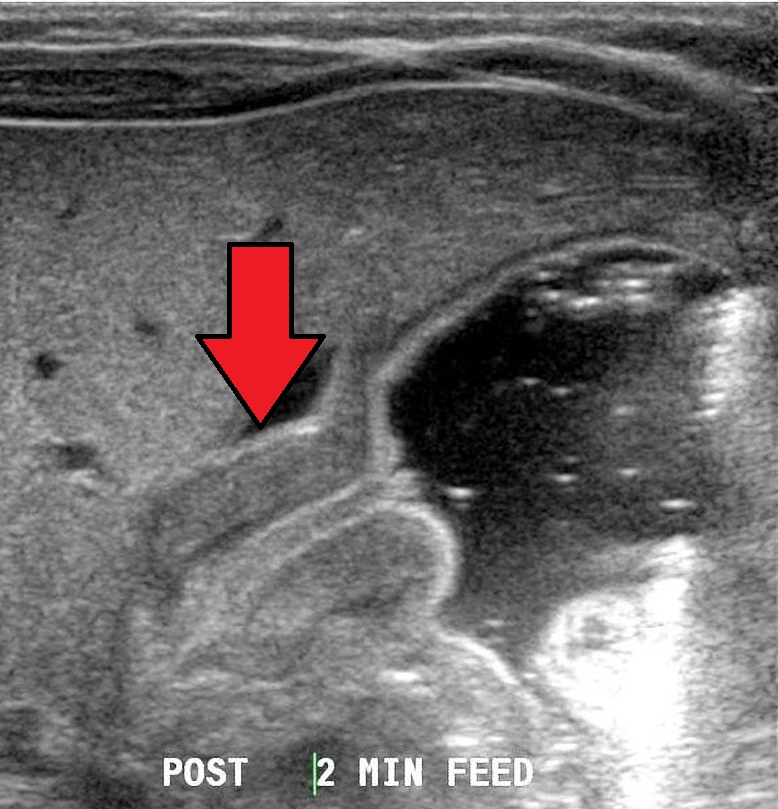

From medicine.uams.edu

Pyloric Stenosis UAMS Department of Radiology How Often Do Babies With Pyloric Stenosis Vomit Pyloric stenosis is a problem that causes forceful vomiting. Pyloric stenosis can make a baby vomit forcefully and often. Symptoms of pyloric stenosis usually appear within 3 to 5 weeks after birth. It affects babies from birth to 6 months of age. The vomit may look curdled, because it stayed in the stomach, where there is acid, and never. Symptoms. How Often Do Babies With Pyloric Stenosis Vomit.